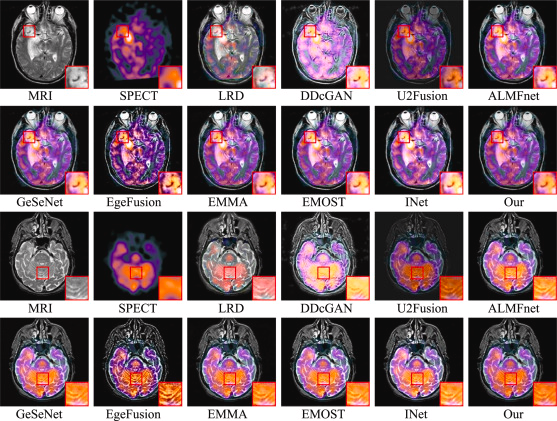

Regarding MRI-SPECT fusion and the developers’ quantitative analysis, they selected two pairs of MRI-SPECT fused images for visualization, as shown in the Figure below. The first and second rows correspond to the first image pair, while the third and fourth rows represent the second image pair. Firstly, the LRD fusion method exhibits severe false color distortion. The DDcGAN method struggles to balance the loss between one generator and two discriminators, resulting in a significant loss of internal detail information. In the case of U2Fusion, the fused images clearly suffer from insufficient brightness, which may increase the difficulty of downstream tasks. As EdgeFusion is based on edge information, its results show overly sharp edges and introduce a considerable amount of noise during the fusion process. Although some other methods perform well in preserving details, they often suffer from overexposure or underexposure in brightness compared to our fusion approach. Therefore, from a visual perspective, LWNet (labeled as “Our” in the figure) achieves superior performance in both detail preservation and brightness balance.

Visualization of two pairs of fused images from the MRI-SPECT dataset for LWNet and comparison methods.